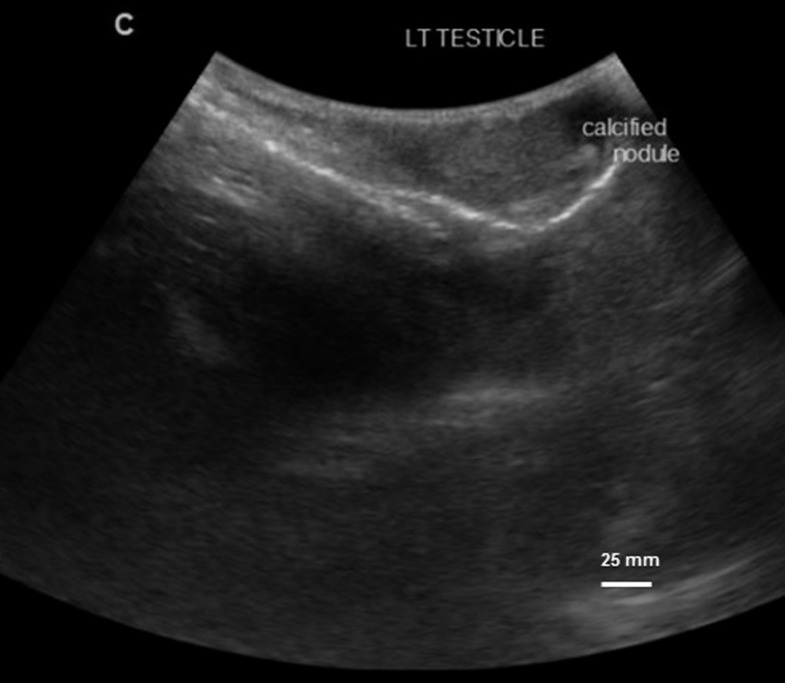

His urine was of normal color with microhematuria (2+) and proteinuria (1+) but no leukocytes, and showed a negative POC-CCA test, and five S. haematobium eggs were observed after filtration. In his 4-mL semen specimen, two eggs and 12 leukocytes were observed using the bag method and three eggs after centrifugation. On ultrasonography, a calcified nodule in the left testis was noted (Figure 2).

Figure 2.

Ultrasonographic image showing genital abnormality, calcified nodule in the left testis for Case 3, observed baseline.